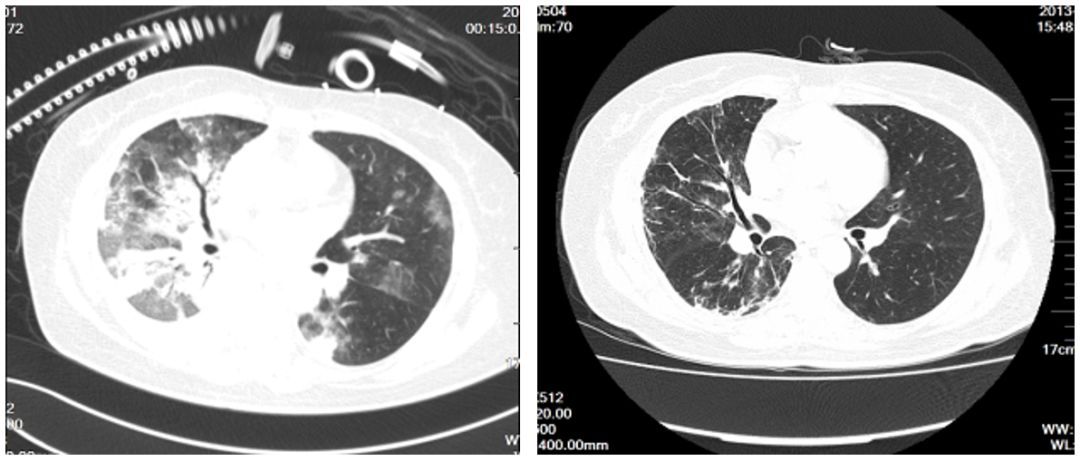

不同病毒所致的肺炎的异同?

如图所示,左边为流感病毒肺炎,右边为RSV病毒肺炎,我们能够从影像学推断病原体吗?尽管最近大家都关注一篇综述性的文章,论述病毒性肺炎的影像学改变,似乎不同的病毒肺炎的影像学具有自身的特点,但是特异性不高。我认为还需要建立一套面向临床需求的病毒学检测方法,才能够更好指导我们的临床诊断与鉴别。